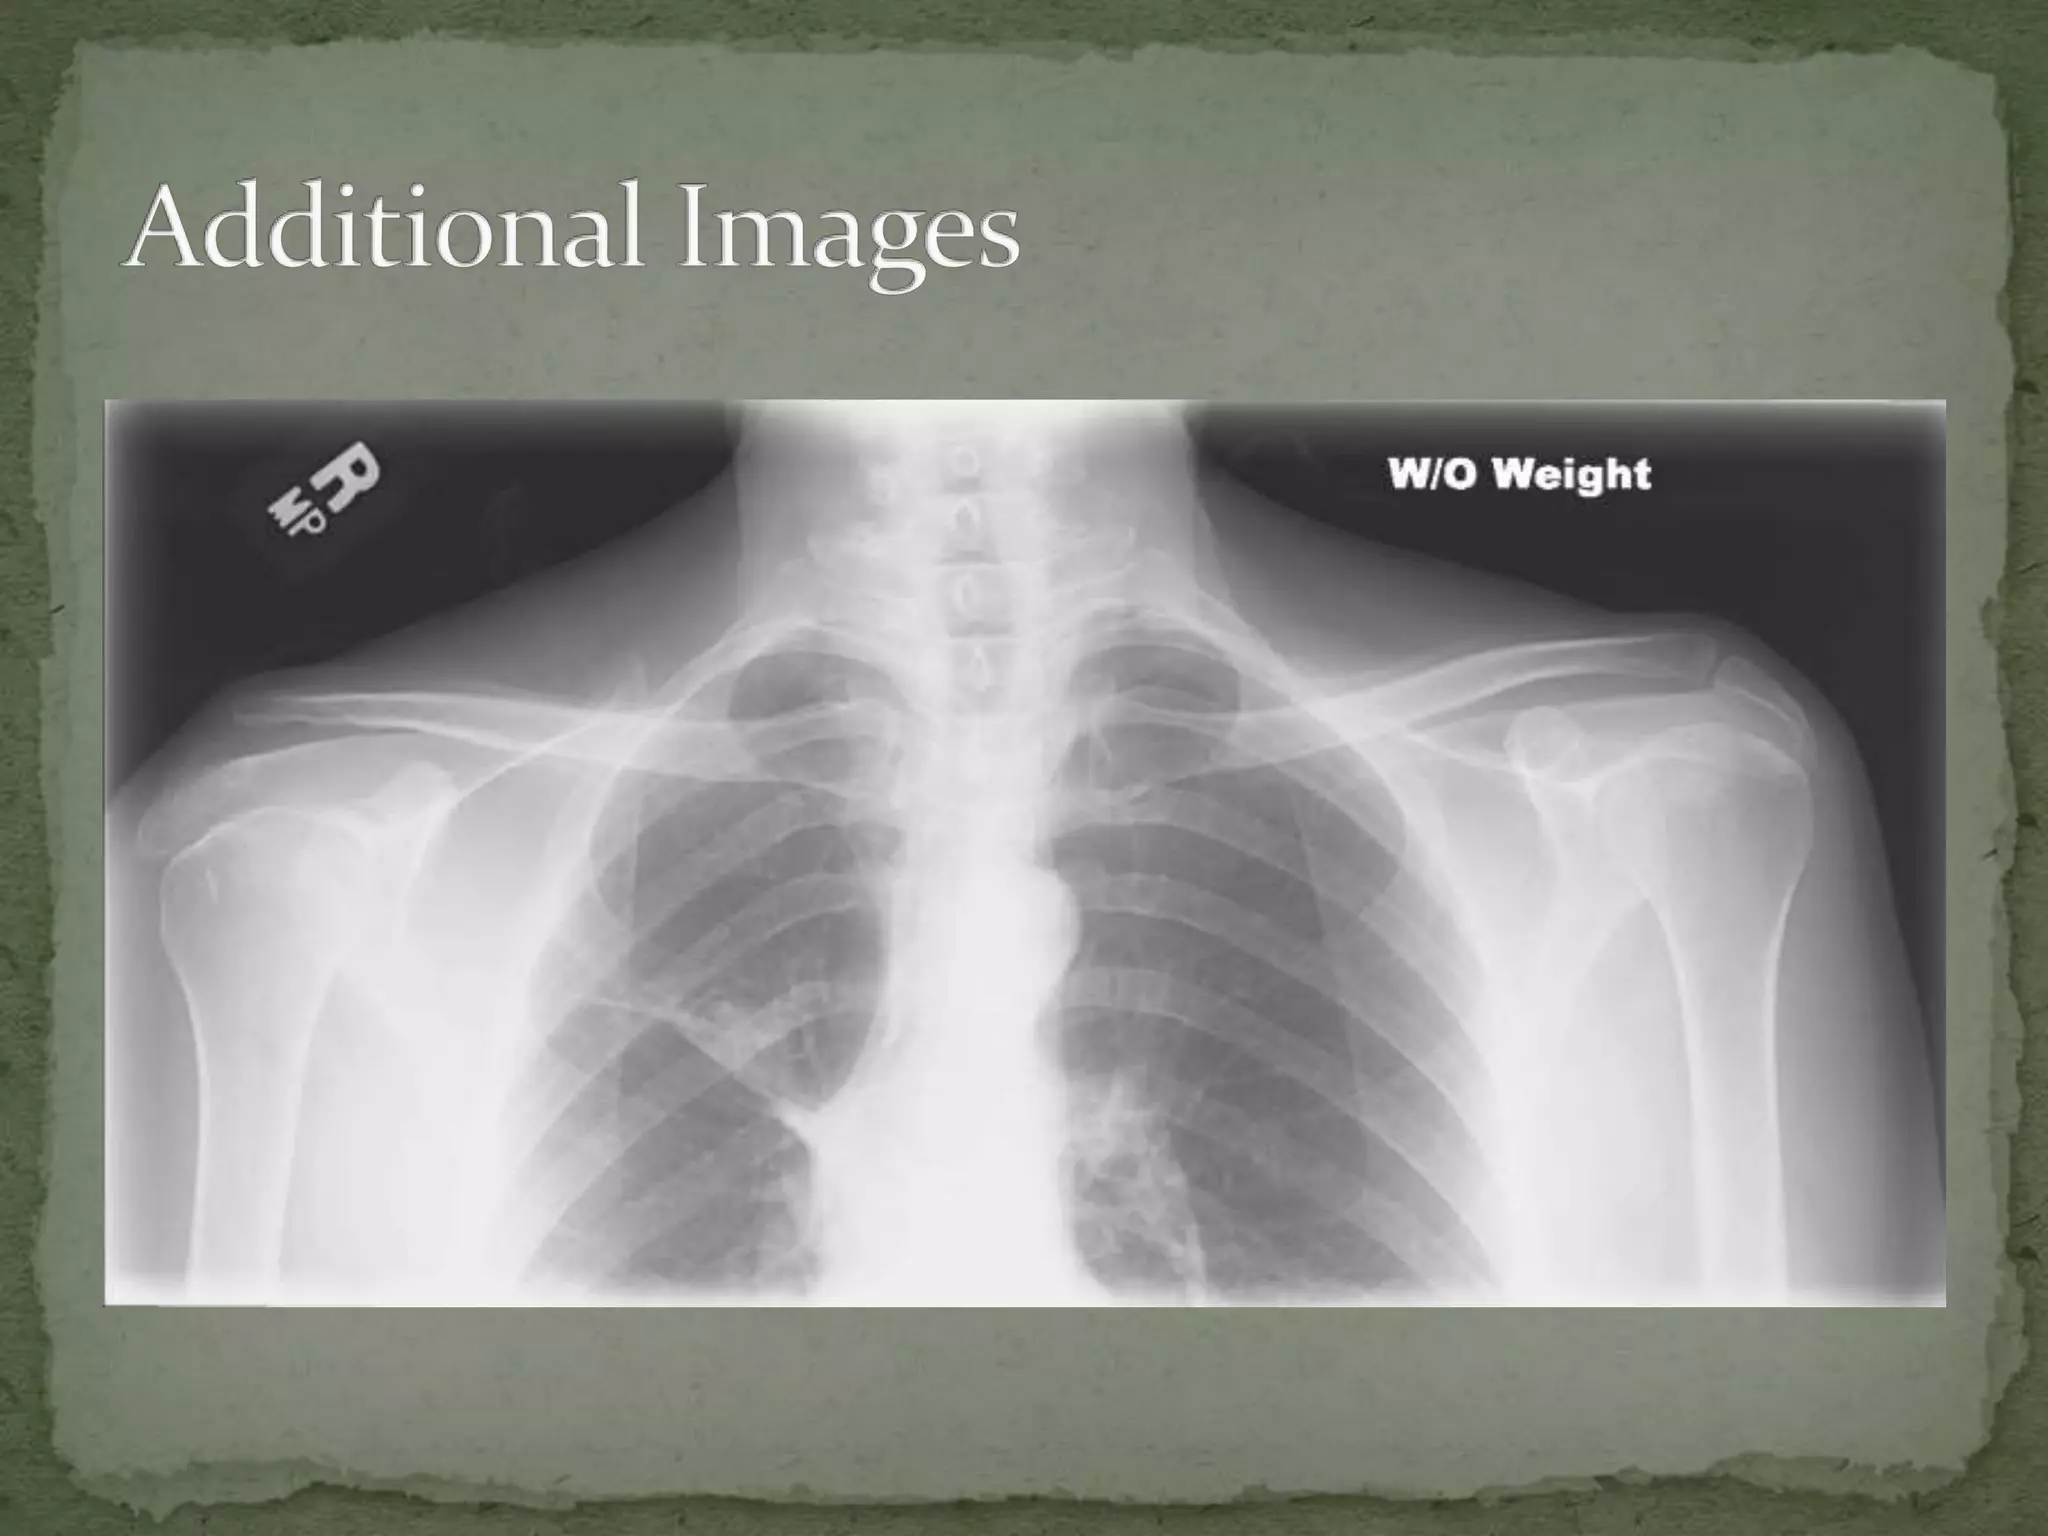

A 42-year-old man presented to the emergency department after being struck in the right shoulder with a baseball bat. On exam, he refused to move his shoulder due to pain and tenderness over the top of the shoulder. Imaging showed widening of the acromioclavicular joint space, indicating an AC joint separation. The separation was likely a Type III injury, with a complete tear of the AC and coracoclavicular ligaments and separation of the AC joint, requiring internal fixation surgery to repair the injury.